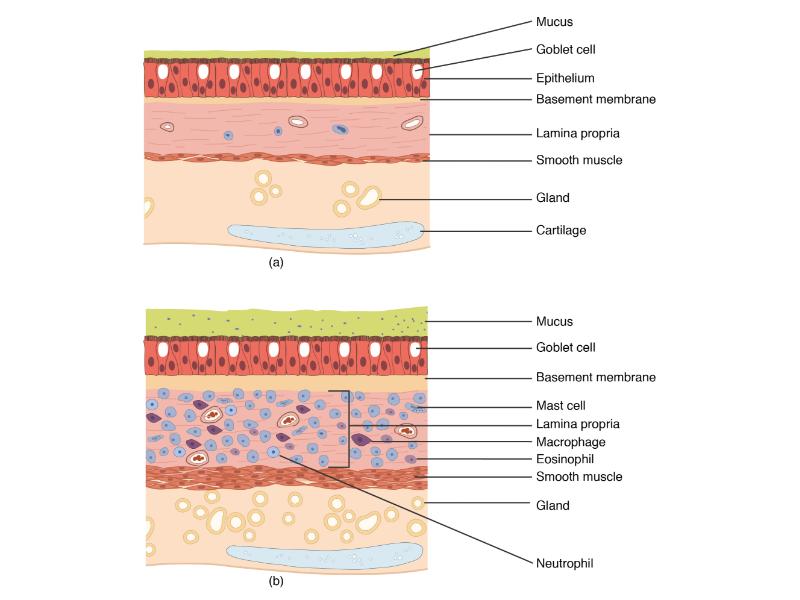

Respiratory epithelium

- Pseudostratified

- Ciliated

- Columnar

- Epithelium with

- 4 Cells

- Ciliated columnar cells

- Non-ciliated columnar cells

- Goblet cells

- Basal cells

Bronchi - Transitions

- Intrapulmonary bronchi

- Irregular cartilage

- Respiratory epithelium

- Glands

- Bronchioles

- Smooth muscle REPLACE cartilage

- Ciliated columnar > Ciliated cuboidal

- NO glands - goblet cells -> secretory cells